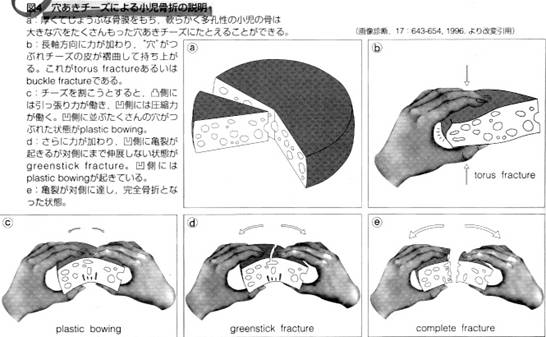

小児の骨格系の特異性に基づき単純X線写真から骨折の画像診断の要点について見逃さないコツを含めて、小児不全骨折と骨端線損傷を中心に画像読影する。

小児不全骨折 A:torus fracture B:greenstick fracture C:plastic bowing

torus fx greenstick fx

greenstick fx plastic

bowing

plastic

bowing